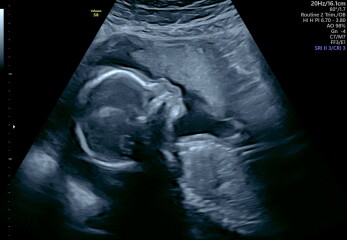

Hi all, had my 20 week scan yesterday. Everything is thankfully going on perfectly in there and there's no concerns. After all my worrying leading up to it I feel a bit numb today about everything baby-wise (although I've been all over with my emotions over the last few months so nothing out of the ordinary really!).

They did a brief 4d bit which I wasn't expecting so I am now too a proud mama to a copper potato :D

@codemytea congrats on the scan - the pics are brilliant!

And @codemytea love the copper potato hahah and congrats that all is well, we got a 4D at early gender scan but it is just so so creepy I’ve barely looked at it haha. Who knew the NHS do this now though? That’s fun!